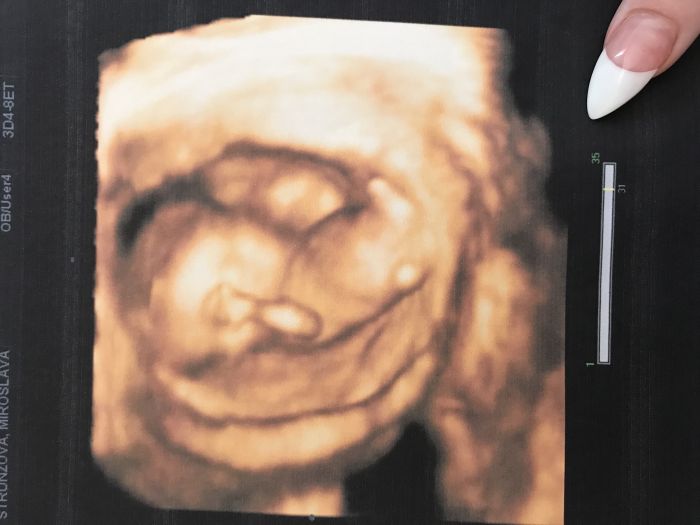

Tak já jsem teď 14+6 a ve 13.tydnu jsem měla krasne zachycené děťátko, už se těším až se dozvím co to bude , příští týden ve středu mám další kontrolu , tak snad už mi to řeknou ❤️

Juu Mirčo ten je krásný! (Nebo ta je krásná

)